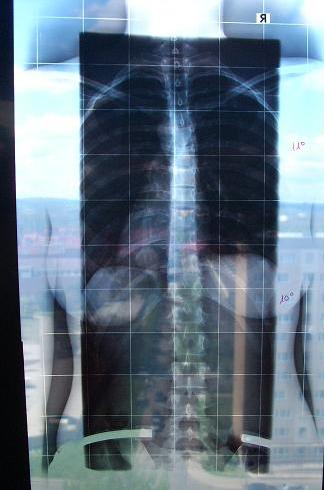

Zuerst stand ich vor ihm, und er meinte, dass ich total schief stehe und den Kopf schief halte. Er rückte meinen Kopf dann erstmal gerade, wodurch sich mein Blick auf die Welt ordentlich verschob. Auf dem Röntgenbild, was meine Wirbelsäule von hinten zeigte, zeigte er mir meine unterschiedlich hohen Schulterblätter. Außerdem zeigte er mir eine Verschiebung der Oberen Brustwirbelsäule, die bis in die Halswirbelsäule ging. Danach war ich erstmal geschockt. Ich hatte diese Verschiebung nie bemerkt. Sie war die Ursache für meine Kopfschmerzen, den schiefen Kopf sowie für die schiefen Schultern. Auf das Röntgenbild wurde dann an dieser Stelle 11° thorakal n. Cobb geschrieben. Bitte schlagt mich jetzt nicht, aber ich war zu durcheinander, um noch mal genau zu fragen, was das heißt. (mit dieser Verschiebung hatte ich nun wirklich nicht gerechnet!) Ich verstehe es so, dass ich dort eine leichte Skoliose habe. Weiter unten in meiner Lendenwirbelsäule hat er nämlich gemeint, habe ich eine leichte Skoliose und die hat 10° lumbal n. Cobb. Dann musste ich mich umdrehen, und er hat meine Hüfte abgetastet. Ich habe unterschiedlich lange Beine, sodass die Hüfte ebenfalls schief steht. Er hat mir dies dann auch auf dem Röntgenbild gezeigt. Da sieht man das auch deutlich. Gleichzeitig sagte er, dass meine unteren Lendenwirbel trotz der Skoliose gerade aufeinander stehen und er deswegen keine Veränderung der Hüfte möchte. Dies würde zu einer Verschiebung der Wirbel führen, die jetzt in einer guten Position wären. Für mich klang das verständlich. Wird die Beinlänge angepasst, ändert sich die Stellung der Hüfte, damit aber auch die Lage der Wirbel. Hat jemand von euch die gleiche Situation?

Dann hat er das Röntgenbild eingeklemmt, welches mich von der Seite zeigt. Er hat eine Kyphose von 52° festgestellt. Dadurch sah meine Lordose auch ganz überdehnt aus.